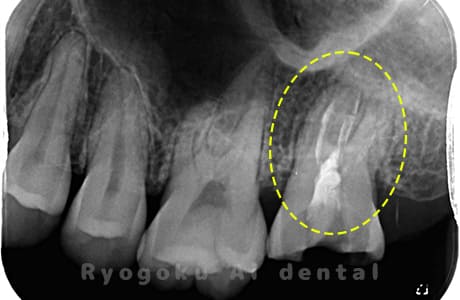

根管内の異物

- 原因

- 根管内異物(ファイル破折)による慢性根尖性歯周炎

- 治療期間

- 3ヶ月

- 治療内容

- マイクロスコープを使用した根管内異物除去並びにマイクロエンド

- 治療費用

- 121,000円(ファイル除去費用も込み)

他院で細い器具(ファイル)が根管内に破折した状態で、咬合痛を主訴に来院された患者様です。ファイルをマイクロスコープ下で除去し、根管治療を行ないました。